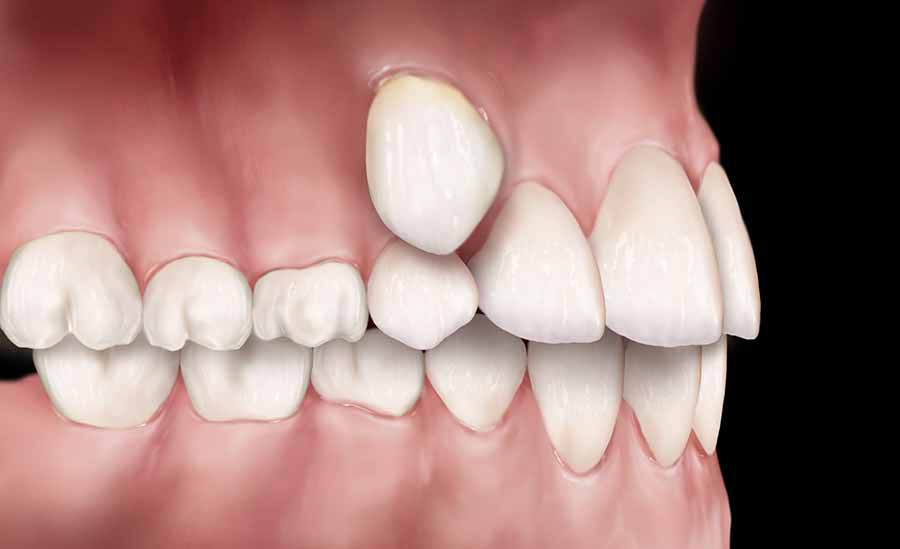

Всем известно, что в ротовой полости должно находиться 32 зуба, это считается нормой. К аномалии количества зубов относится их избыточное количество, а также недостаток или полное отсутствие. Первая проблема имеет название – гипердонтия, и для нее характерно наличие сверхкомплектных зубов, которые находятся не в зубном ряду, а за его пределами и сильно смещают своих соседей в стороны, тем самым, меняя их нормальное положение на патологическое. Сверхкомплектные зубы чаще можно обнаружить на верхних рядах, их размеры и форма не совпадают с принятыми нормами. Довольно редко случается так, что сверхкомплектный зуб удачно втиснулся в зубной ряд.

Такие зубы необходимо удалять в обязательном порядке, поскольку они нарушают построение зубных рядов. После их удаления проводится коррекция положения постоянных зубов, ведь они были сильно смещены при образовании сверхкомплектных. С этой целью проводится ортодонтическое лечение. Если же больному повезло и лишний зуб удачно вписался в ряд и не мешает нормальному развитию соседей, то его можно оставить. Следует лишь исправить его форму на правильную. А сделать это очень просто при помощи протезирования.